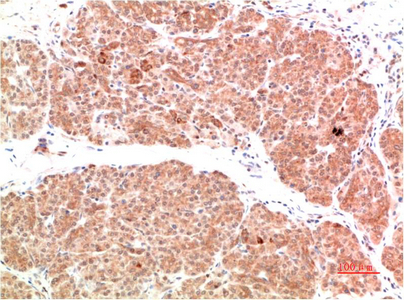

PI 3 Kinase P85 Rabbit Polyclonal Antibody

Applications

IHC, IF

IHC 1:100-200; IF 1:50-200